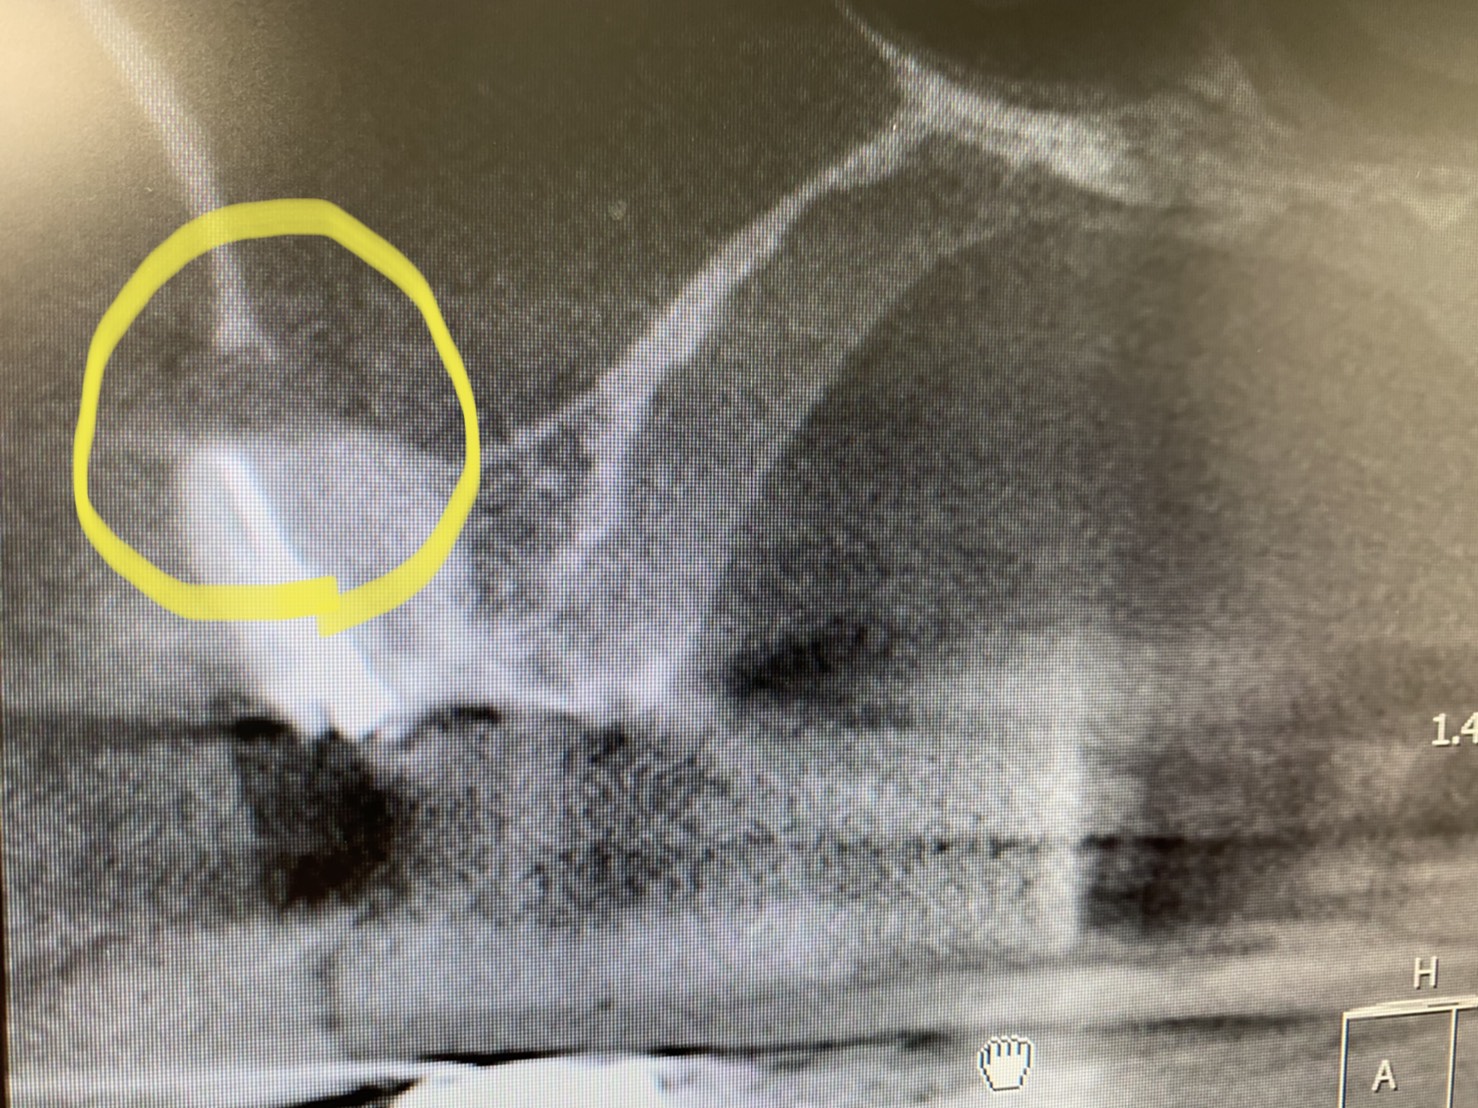

根管の尖端付近が枝分れしています

このようにな『側枝』が空洞化していると、根管の感染が再燃する一因になります。

普通の根管充填方法ではストレートの本管しか充填材は入りません💦

このような湾曲した細い枝に充填出来るのは、NT(ニッケルチタンファイル)オブチュレーションシステムを採用しているからです。

C Tでも分かりますね